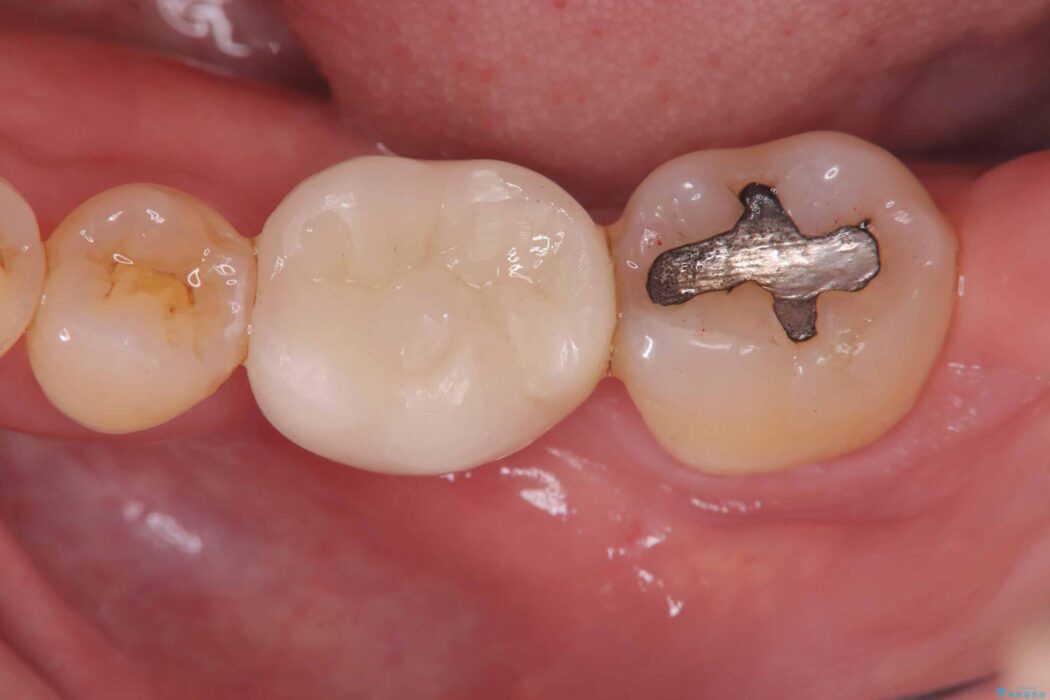

レントゲン検査にて、根尖および側枝付近に骨の透過像が認められました。

さらに精査したところ、根のパーフォレーション(根に穴が開いてしまっている状態)が確認されたため、

患者様と相談のうえ、インプラントにて治療を行うこととしました。